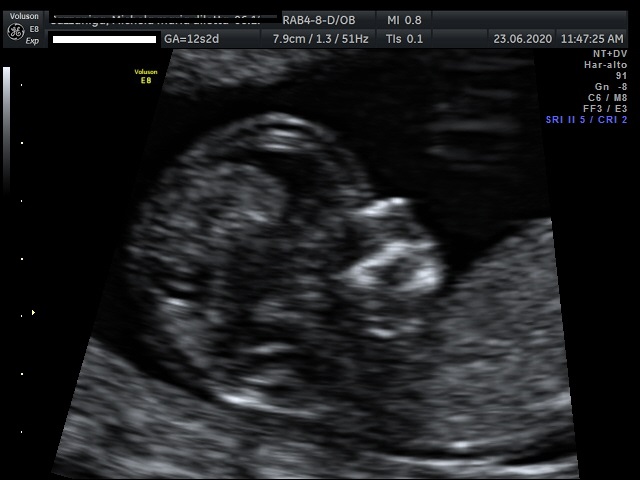

- Gravidanza e principali patologie ostetriche, Ecografie ostetriche, Patologia ginecologica, Ecografia ginecologica. Infertilità.

Foto e Video